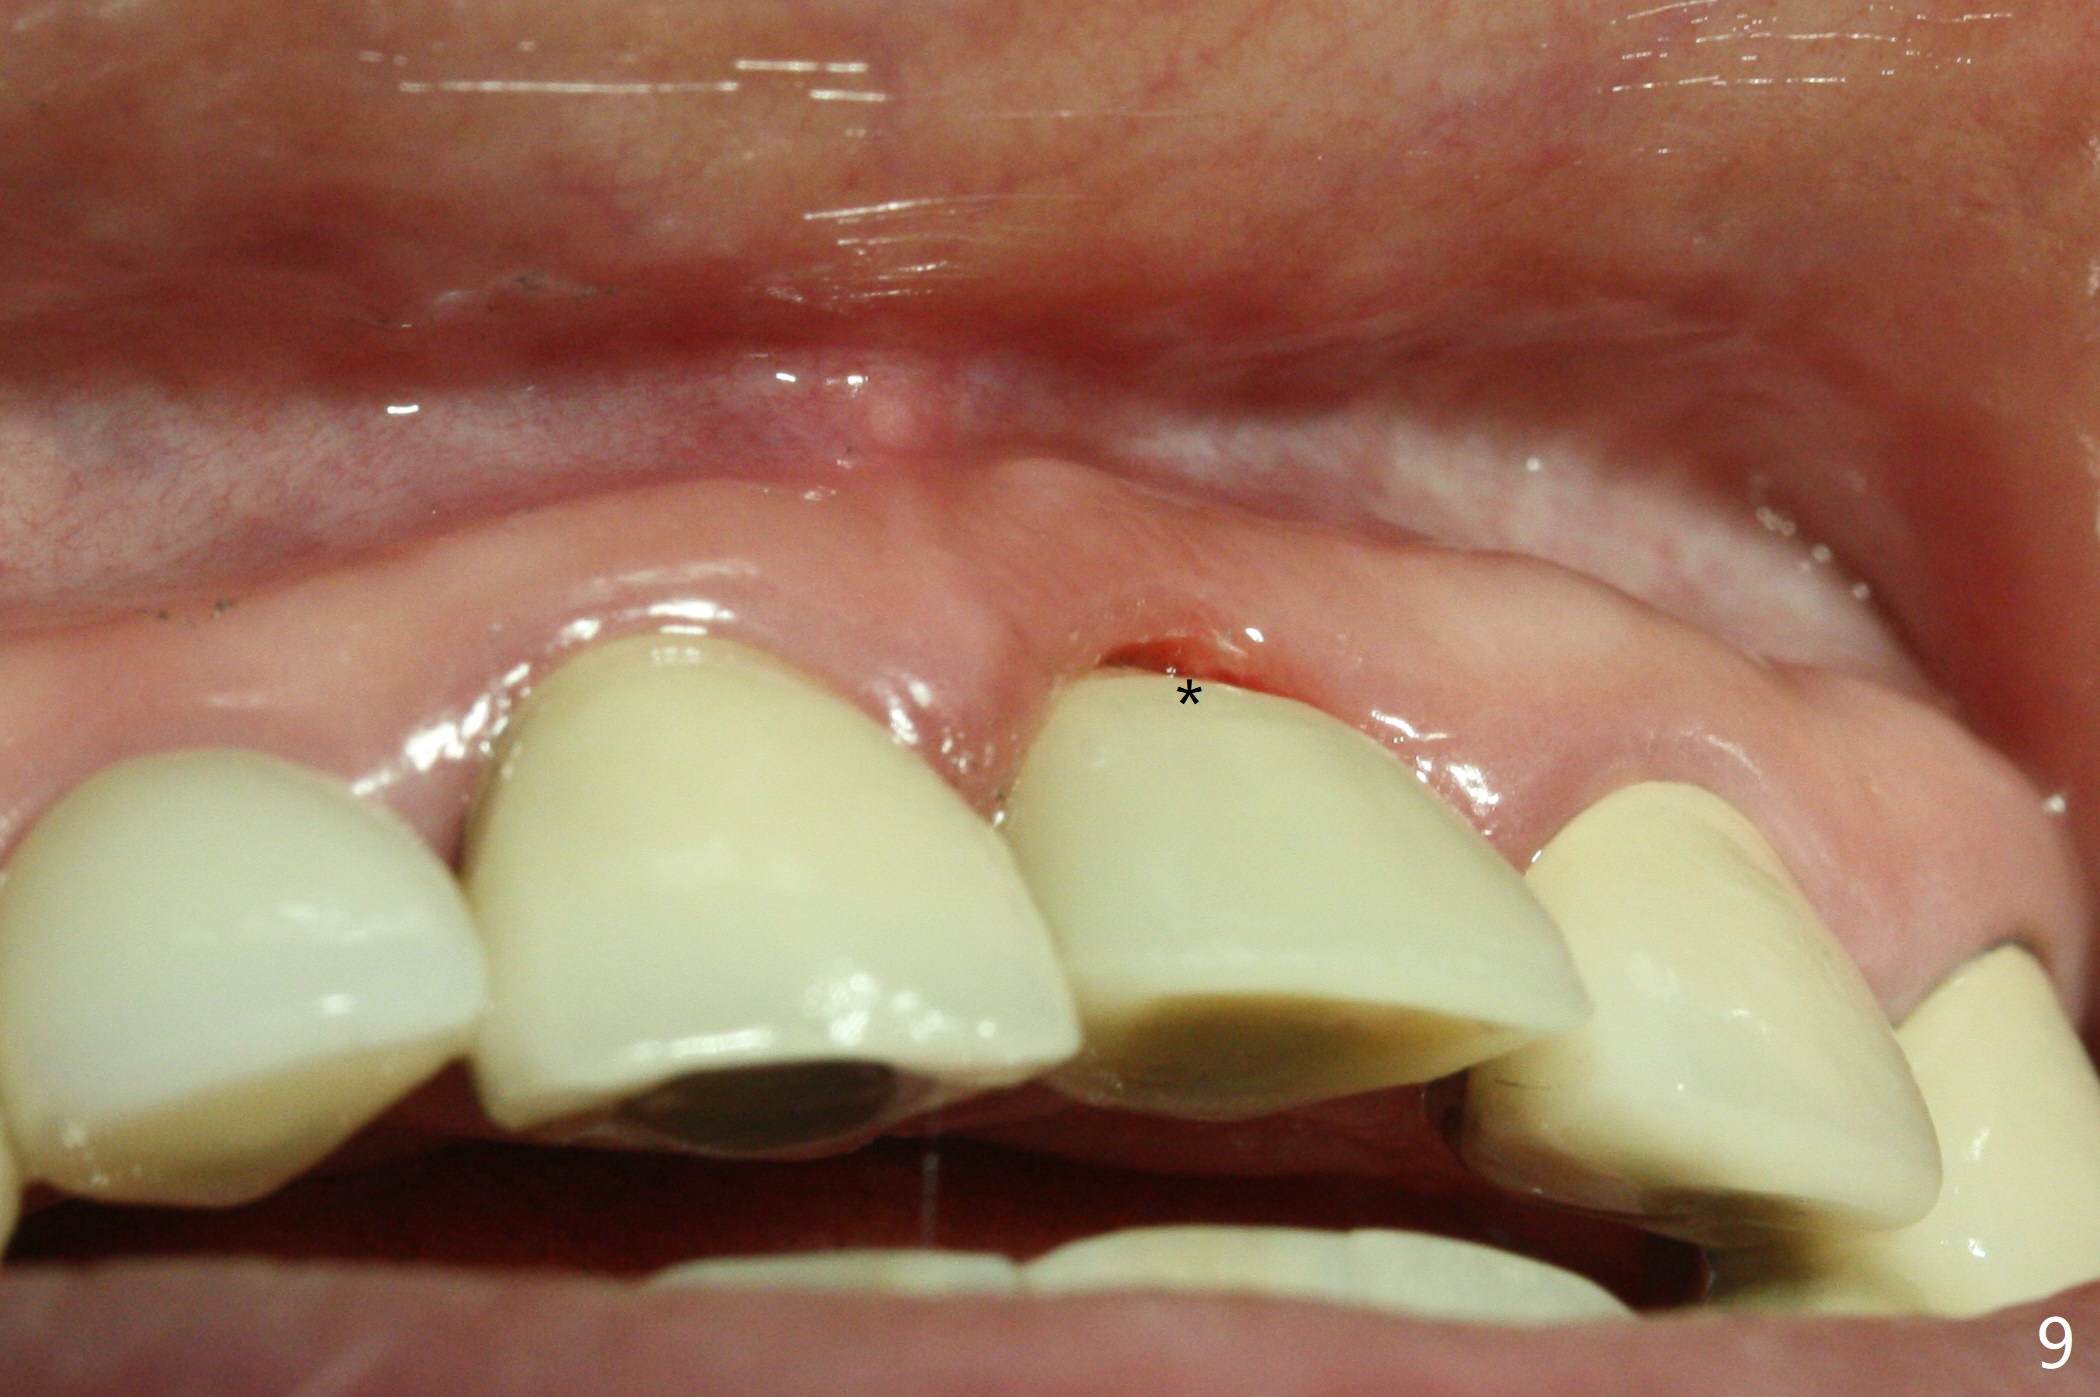

3.8x15 mm Implant with Proximity to

Nasal Floor

The buccal contour at #9 seems to be slightly concave preop (Fig.1,2 (*)). In fact the buccal plate is found to be lost when the tooth is extracted. Osteotomy is initiated as palatal as possible apical, but the occlusion dictates the coronal end of the osteotomy should be buccal, leaving the buccal gap ~ 2 mm for bone graft. The initial osteotomy (18 mm deep) appears to be close to the Incisive Foramen (Fig.3 blue dashed line). The nasal floor appears to be intact when the drill is removed. Subsequent osteotomy is adjusted so that the apical end of the osteotomy moves distal; when a 3.8x15 mm dummy implant is partially placed, there is clearance (Fig.4). It remains so when a definitive implant is seated (Fig.5); Vanilla graft is placed (Fig.5 *) before placement of a 4.5x5.5(3) mm abutment. More allograft is placed when an immediate provisional is fabricated (Fig.6 arrow and *). The gingiva remains to be recessive 1 month postop (Fig.7). It seems to be related to the bulky gingival margin of the provisional (Fig.8 *). After trimming the latter (Fig.9 *), the gingival margin immediately returns close to normal (Fig.10). The gingival margin is even between #8 and 9 two months postop, but the bone graft is exposed apically (Fig.11 ^). It may heals by itself. Otherwise debridement, regraft, PRF and suture are pending. The coronal portion of the socket heals 4 months postop (Fig.12). The gingival cuff forms by the immediate provisional (which is removed for impression) 4 months postop (Fig.13 *). While the full Zirconia crown at #7 remains intact (Fig.14), the PFM at #9 has porcelain chip (Fig.15). It is partially due to the occlusion; while the crown at #7 has clearance with the opposing dentition (Fig.16 *), the one at #9 has no. The access hole at #9 (Fig.17 *) seems to weaken the crown structure. There is no access hole at #7. No solid posterior support is another contributing factor for chip (Fig.18). The buccal plate has mild atrophy at #7 and 9 (Fig.19 *). A piece of bone graft is being expelled apically at #9 (Fig.20 >) and is removed subsequently (Fig.21). Before impression for repacking porcelain, the opposing incisal edge has been shortened (Fig.22 arrows, as compared to Fig.16). Since the ideal access hole is at the incisal edge (Fig.25 black circle), buccal to the existing one (Fig.24 A), the abutment is torqued before the repaired crown is recemented (Fig.23). Finally the crown has occlusal clearance (Fig.26). Porcelain chips again around the access hole of PFM 1.5 years post 2nd cementation. The dense bone at the crest (*) cannot explain why the abutment is not loose, since it remains incompletely seated (>). As it was trimmed short, an angled abutment is used (Fig.28). The coronal end is lingual, while #9/24 is edge to edge. The lingual aspect of the coronal end of the abutment is heavily trimmed to reduce bulkiness. To prevent chip, Zirconium crown will be fabricated in spite of the fact that it does not match the PFM of #8 (potential shade discrepancy). The patient is pleased with the new Zirconia crown (Fig.29).